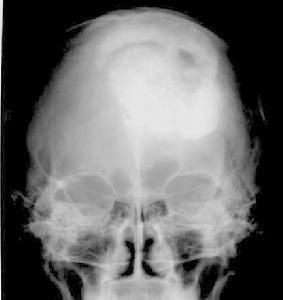

顱骨結核大體可見在與受累的顱骨相應部位的頭皮下有寒性膿腫,內含乾酪樣壞死組織及至膿腫破潰後形成的竇道。顱骨呈棕灰色,無光澤,質鬆軟常有形狀不同的骨缺損或死骨。顯微鏡下可見皮下及竇道內和硬腦膜外有大片乾酪樣壞死及纖維結締組織增生,顱骨的骨小梁正常結構遭到破壞,分辨不清。